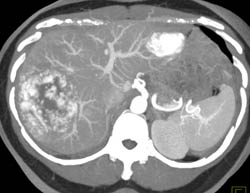

Giant Cavernous Hemangioma